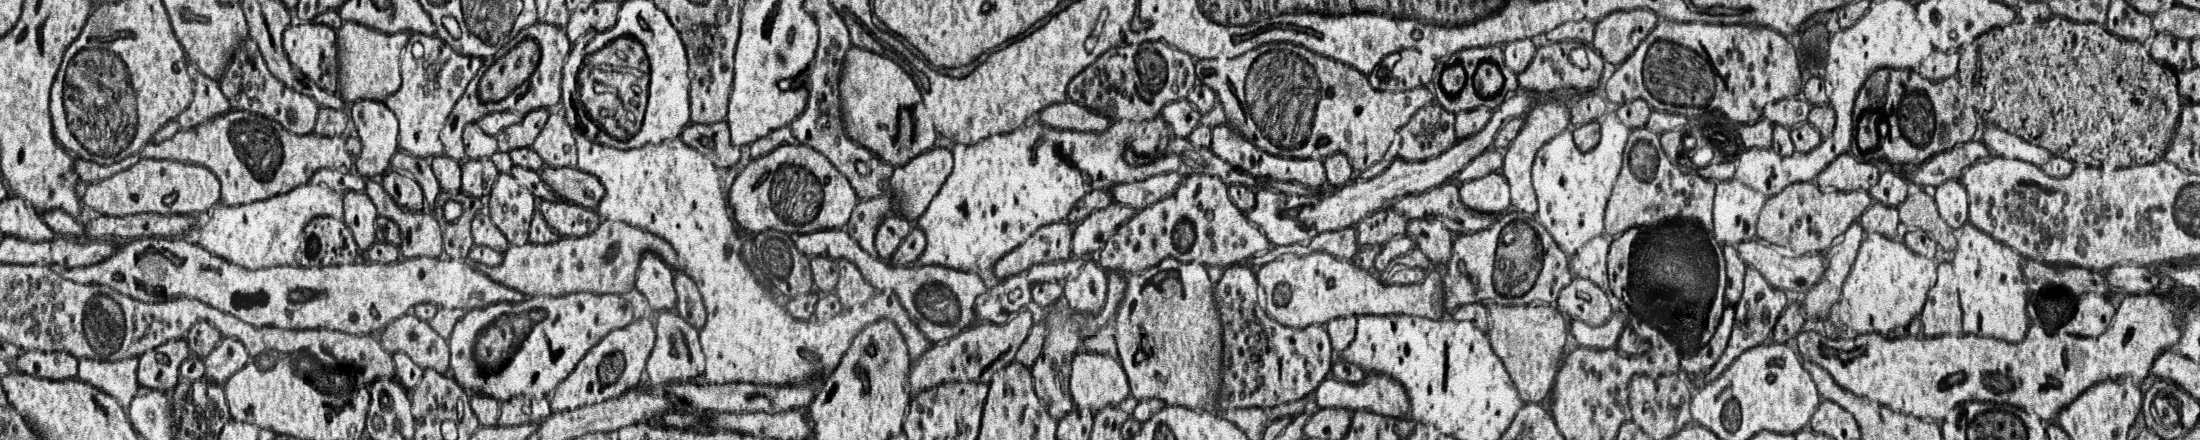

The task is the 3D mitochondria instance segmentation on two 30x30x30 um datasets, 1000x4096x4096 in voxels at 30x8x8 nm resolution. The image volumes are acquired from a rat (Mito-R) and a human (Mito-H) tissue, respectively. The mitochondria can display a complex morphology, e.g., (a) mitochondria-on-a-string (MOAS) instances are connected by thin microtubules, and (b) multiple instances can entangle with each other.